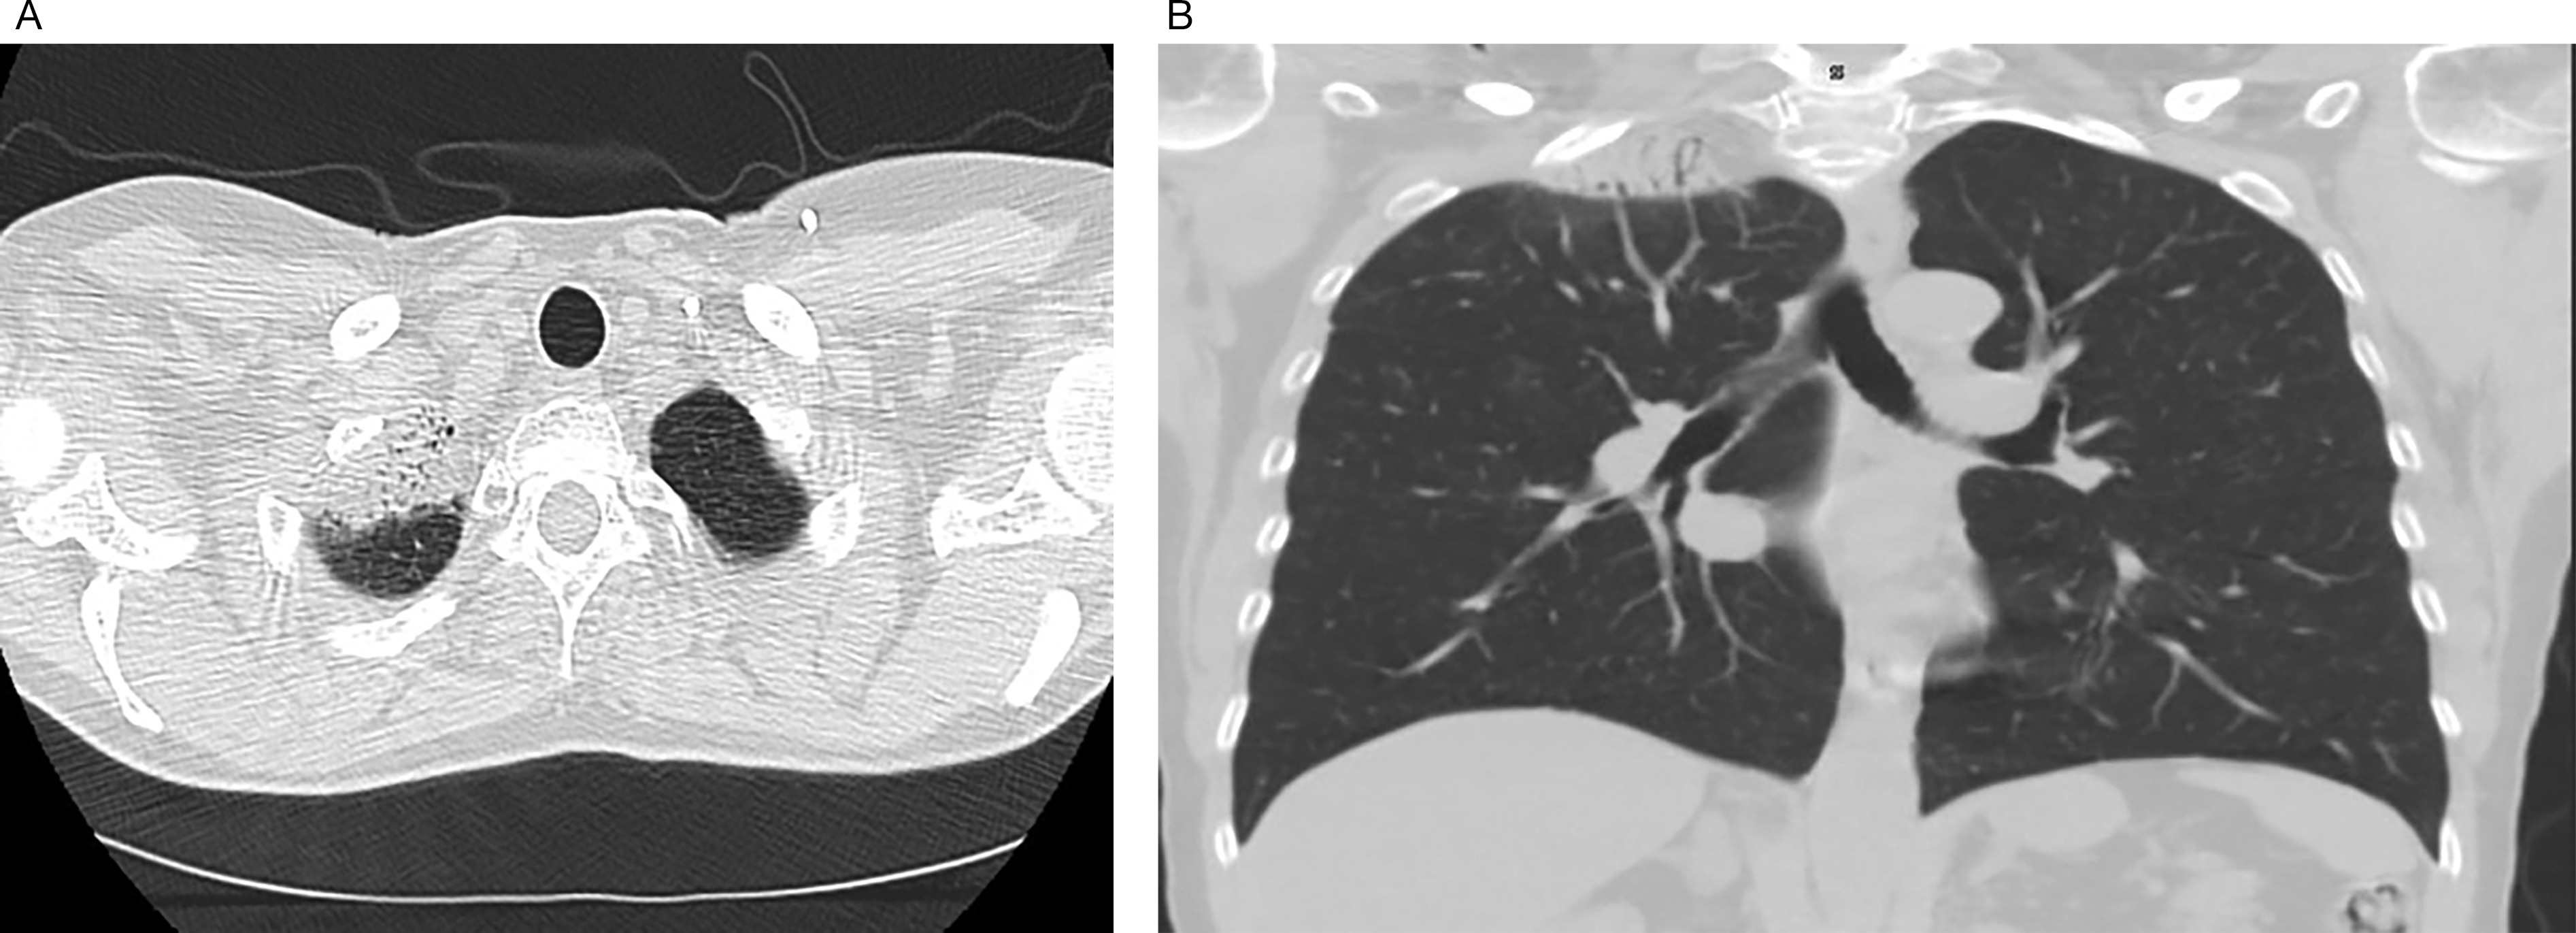

The patient developed cutaneous symptoms, which progressed to telangiectasias and significant fibrosis (Figure 1). In addition, she developed radiographically detected asymptomatic radiation pneumonitis (Figure 2A-B).